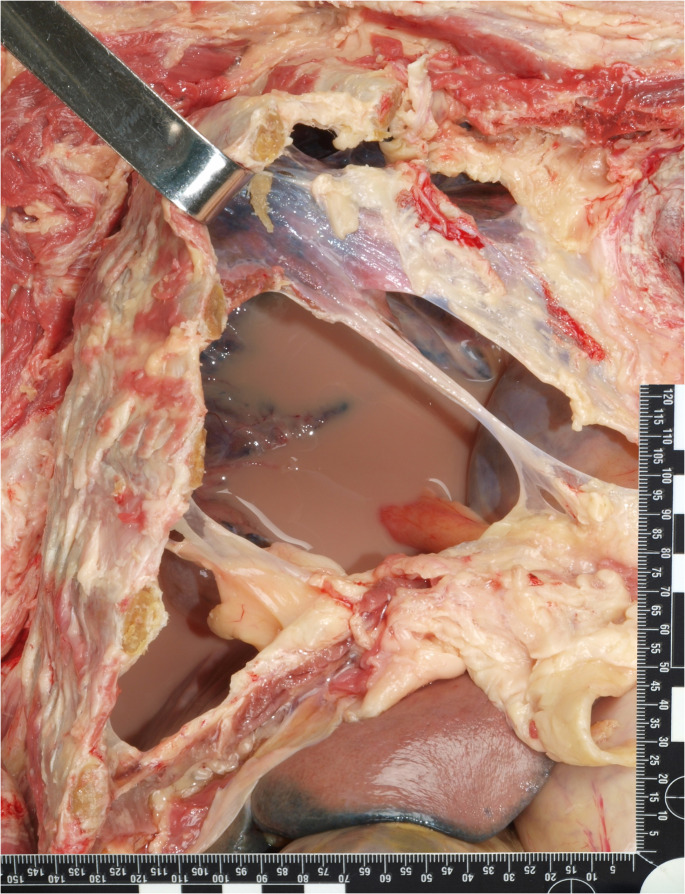

Results: The autopsy revealed milky, turbid pleural effusion, aspiration pneumonia, and a rupture of the right visceral pleura. Cytological analysis confirmed granulocytic pleural empyema with rod-shaped Congo red-positive material resembling the enteral nutrition formula. Gas chromatography-mass spectrometry identified tricaprylin, a unique marker for enteral nutrition formula, confirming nutritional leakage into the pleural cavity.